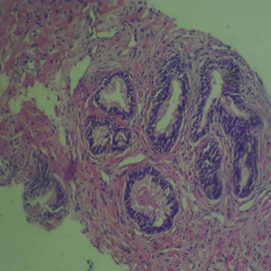

The mean percentage reactivity of immunohistochemistry biomarkers was presented in Figure 1. The results showed a gradual increase in percentage reactivity in MLH1 and MSH2 from BPH to prostate cancer. Figure 2 displayed Hematoxylin and Eosin-stained sections of control tissue samples at x100 and x400 magnification, respectively. Figure 3 presented Hematoxylin and Eosin-stained sections of MLH1 expression in BPH and PC at x100 and x400. The result of (A) showed mild expression of MLH1 in benign prostatic hyperplasia at x100, (B) exhibited moderate expression of MLH1 in prostate cancer at x100, (C) showed mild expression of MLH1 in benign prostatic hyperplasia at x400, and (D) demonstrated moderate expression of MLH1 in prostate carcinoma at x400. Figure 4 displayed Hematoxylin and Eosin-stained sections of MSH2 expression in BPH and PC at x100 and x400. The results of (A) showed mild expression of MSH2 in benign prostatic hyperplasia at x100, (B) displayed moderate expression of MSH2 in prostate carcinoma at X100, (C) illustrated mild expression of MSH2 in benign prostatic hyperplasia at x400, and (D) demonstrated moderate expression of MSH2 in prostate carcinoma at x400.

Figure 2 Haematoxylin and Eosin-stained sections (Control i.e. images refer to regions coming from normal tissue adjacent to the tumor); (A) x100 BPH (B) x100 PC (C) x400 BPH (D) x400 PC